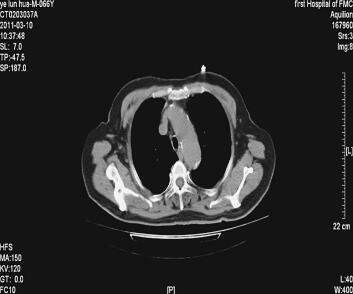

诊治经过:入院后查血常规:WBC 8.59×109/L,N 71.1%;血气分析:pH 7.387,PaO2 39mmHg,PaCO2 49.4mmHg;生化:空腹血糖7.30mmol/L,TC 5.18mmol/L,LDL-C 3.91mmol/L,CK-MB 18U/L;HbA1C 7.4%;CRP 8.69mg/L(0~8mg/L);PCT 0.09ng/ml(0~0.05ng/ml);D-二聚体139.8μg/L(< 342μg/L),GFR 93.44ml/min;BNP 363.65pg/L(0~100pg/L);肌钙蛋白I(TnI)2.406μg/L(0~0.78μg/L);电解质、肝肾功能正常;心电图:频速型房颤,左前分支阻滞,左心室肥大伴劳损,部分导联ST段抬高(图1);肺部CT:右肺中叶慢性炎症,心影增大,主动脉硬化(图2);肺功能检测:FEV1 26.9%,FEV1/FVC 90.1%。结论:混合型肺通气功能障碍。

图2 右肺中叶慢性炎症,心影增大,主动脉硬化